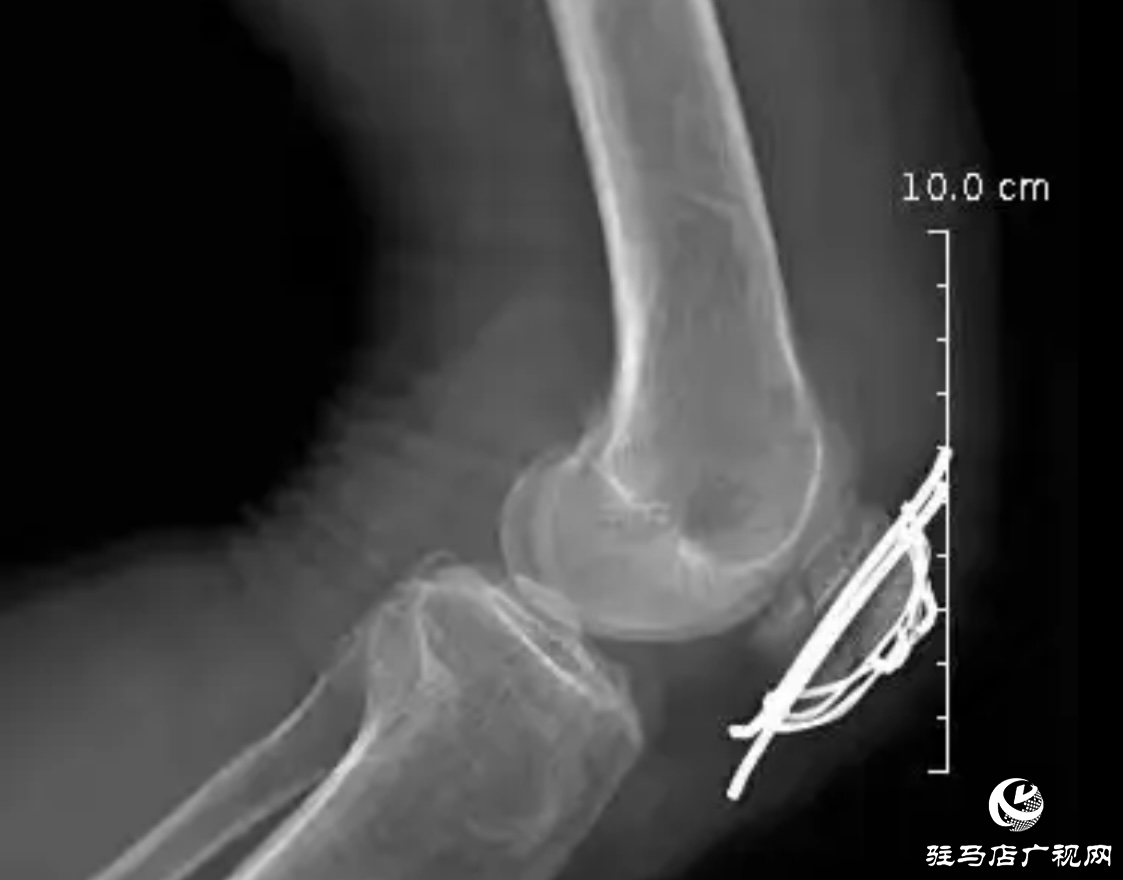

8月5日,正陽縣皮店鄉(xiāng)衛(wèi)生院外科團隊成功為一位高齡患者范老奶奶實施“左側髕骨骨折切開復位內固定術”,以專業(yè)的醫(yī)術和貼心的護理,幫助了老人擺脫了骨折痛苦,重拾行走希望,贏得了家屬及周邊群眾的廣泛贊譽。

范老奶奶在家中不慎摔倒,導致左膝劇烈疼痛、明顯腫脹,無法站立行走。家人立即將其送往正陽縣皮店鄉(xiāng)衛(wèi)生院就診。經檢查,確診為左側髕骨骨折,需進行手術治療。鑒于患者年事已高,身體機能較弱,手術和麻醉風險相對較高,皮店鄉(xiāng)衛(wèi)生院外科團隊高度重視,迅速組織病例討論,全面評估患者心肺功能及基礎疾病情況,為老人精心制定了周密的手術方案及術后康復護理計劃,力求最大限度降低手術風險,確保手術安全、順利。

手術過程中,皮店鄉(xiāng)衛(wèi)生院外科團隊配合默契、操作精準,順利完成了骨折復位與內固定術。整個手術過程高效順暢,耗時短、創(chuàng)傷小,充分體現了團隊扎實的專業(yè)技術與嫻熟的協作能力。術后,醫(yī)護人員對范老奶奶給予了精心護理,密切關注老人的恢復情況,并根據康復計劃指導患者開展早期功能鍛煉。目前,范老奶奶傷口愈合良好,疼痛顯著緩解,左膝關節(jié)已能逐步進行主動活動,康復進展理想。家屬對治療效果高度認可,多次向醫(yī)護人員表達誠摯謝意,稱贊衛(wèi)生院不僅技術過硬,更充滿人文關懷。